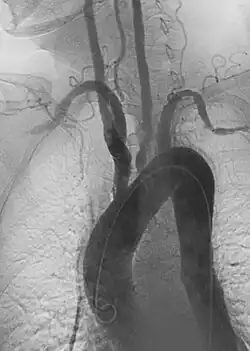

1. Aortic aneurysms include thoracic, abdominal and thoracoabdominal aneurysms. Treatment strategies are customized depending on the location, size, rate of growth and extent of the aneurysm as well as the medical comorbidities of the patient. For example, an intact, small but slowly growing aneurysm may be safely monitored with serial imaging for months or years before elective repair is considered. Elective endovascular aortic grafting is now routinely attempted when possible. Endovascular aortic repair (EVAR) refers to treatment of an abdominal aortic aneurysm, while thoracic endovascular aortic repair (TEVAR) is performed on the thoracic aorta. A ruptured aneurysm may be taken emergently for open, endovascular or combination repair.

A variety of endovascular grafts are available, and each has advantages and disadvantages depending on the characteristics of the aneurysm and patient.[90]